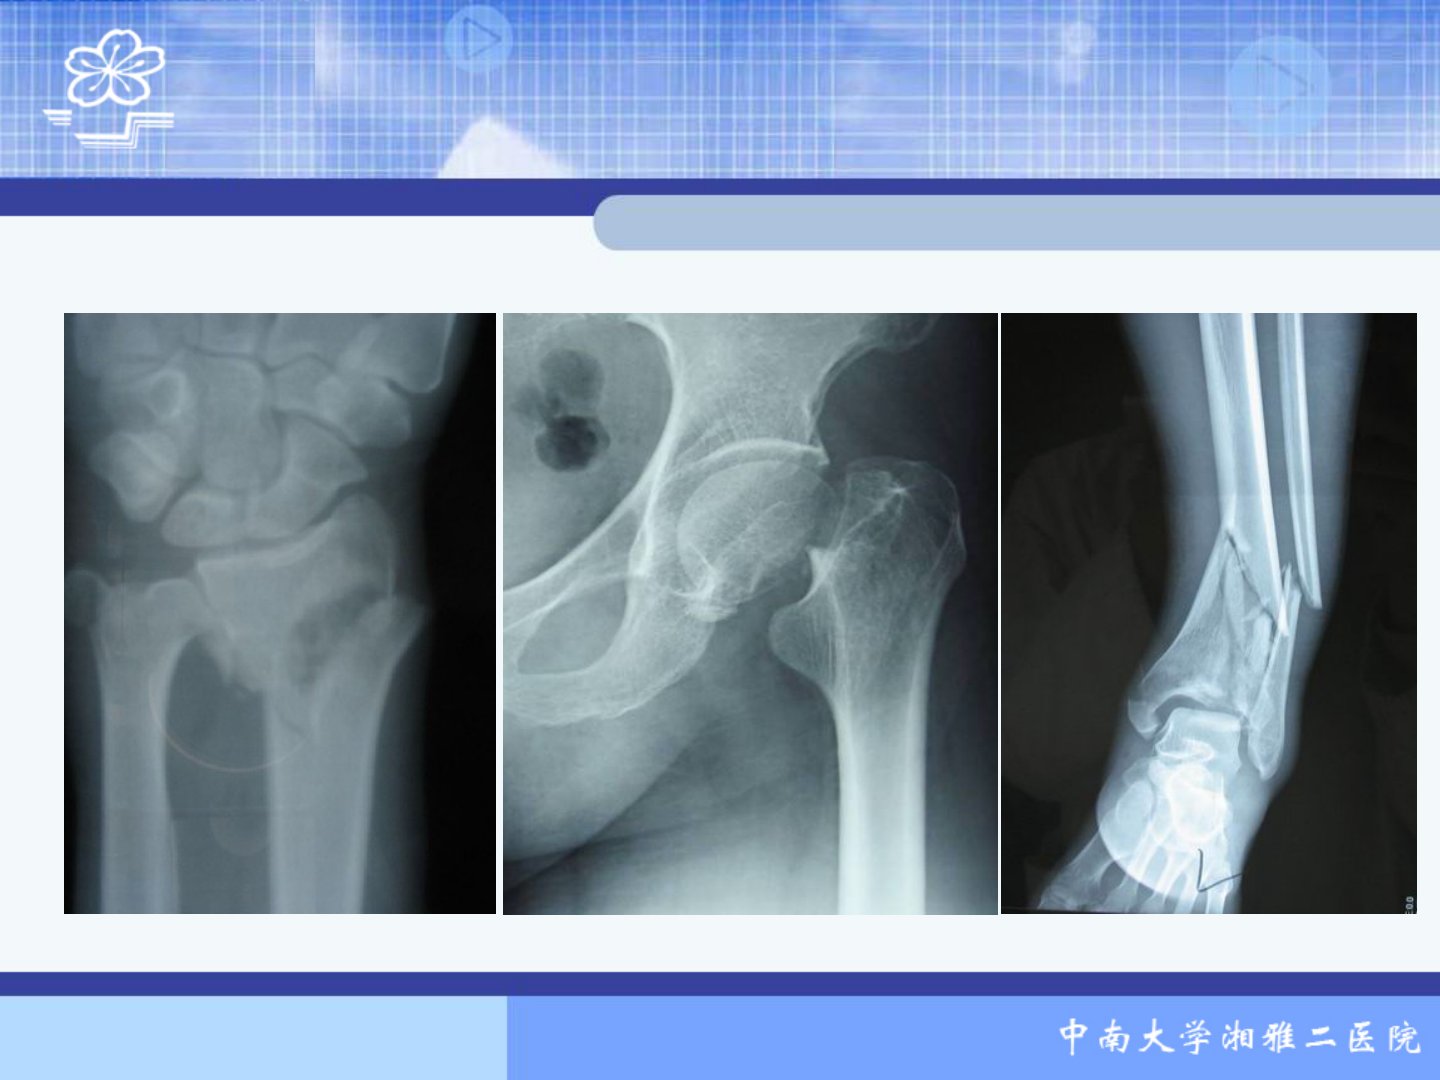

骨折概论摘要本文是中南大学湘雅二医院骨科王万春关于骨折的综述主要内容如下:1骨折定义与成因:骨折指骨的完整性和连续性中断成因包括直接暴力、间接暴力、积累性劳损及骨骼疾病。2骨折分类与移位:分为闭合性和开放性骨折;按程度和形态分不完全和完全骨折;按骨折端稳定程度分稳定性和不稳定性骨折。骨折移位受暴力性质、肌肉牵拉、肢体重量及搬运治疗影响。3临床表现与X线检查:全身表现有休克、发热;局部表现包括疼痛、肿胀等一般表现及畸形等特有体征。X线检查对骨折诊断治疗价值重要。4骨折并发症:早期有休克、脂肪栓塞综合征等;晚期有坠积性肺炎、压疮等。5骨折愈合过程:分为血肿炎症机化期、原始骨痂形成期、骨板形成塑形期。6影响骨折愈合的因素:全身因素包括年龄、健康状况;局部因素有骨折类型、血液供应、软组织损伤等;治疗方法不当也会影响愈合。7骨折的急救:包括抢救休克、包扎伤口、妥善固定、迅速转运。8骨折的治疗原则:包括复位、固定、康复治疗。9开放性骨折的处理:分类后进行术前检查准备及时清创修复组织、闭合创口。10开放性关节损伤处理原则:与开放性骨折处理原则基本相同目的为防止关节感染和恢复关节功能。11特殊情况处理